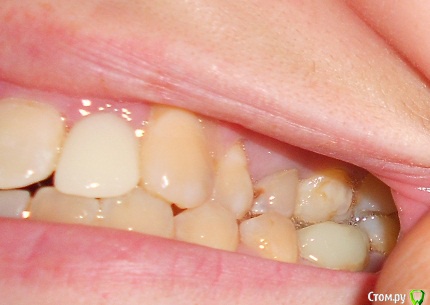

Добрый день, прошу проконсультировать, как поступить в моей ситуации.Прикус как могла сфоткала, сейчас проблема в отсутствии 2х верхних резцов, на их место поставила импланты-но они не прижились-в качестве наиболее вероятной причины выдвигают-недостаточность места, близость к корням соседних зубов.Возможно ли в моем случае ситуацию исправить брекетами.Прикус по-моему неправильный, ВЧ узкая, перекрытие НЧ есть в р-не передних зубов и задних, в середине картина не очень.Возможно ли немного расширить ВЧ. И беспокоит не будут ли смещаться зубы на место отсутствующих?Сейчас на месте одной из двоек съемная бабочка на месте другой имплант который нужно удалять.

Вы правильно обрисовали картину. У вас дефицит места для  "двоек" ,  также перекрестный прикус слева  (справа Вы не показали) (обратное перекрытие зубов, что чревато для сустава.) Также отсутствие верхнего бокового зуба ("пятерка"),  также ретенированные восьмерки (их надо удалять), ну и качество пролеченных зубов оставляет желать лучшего.